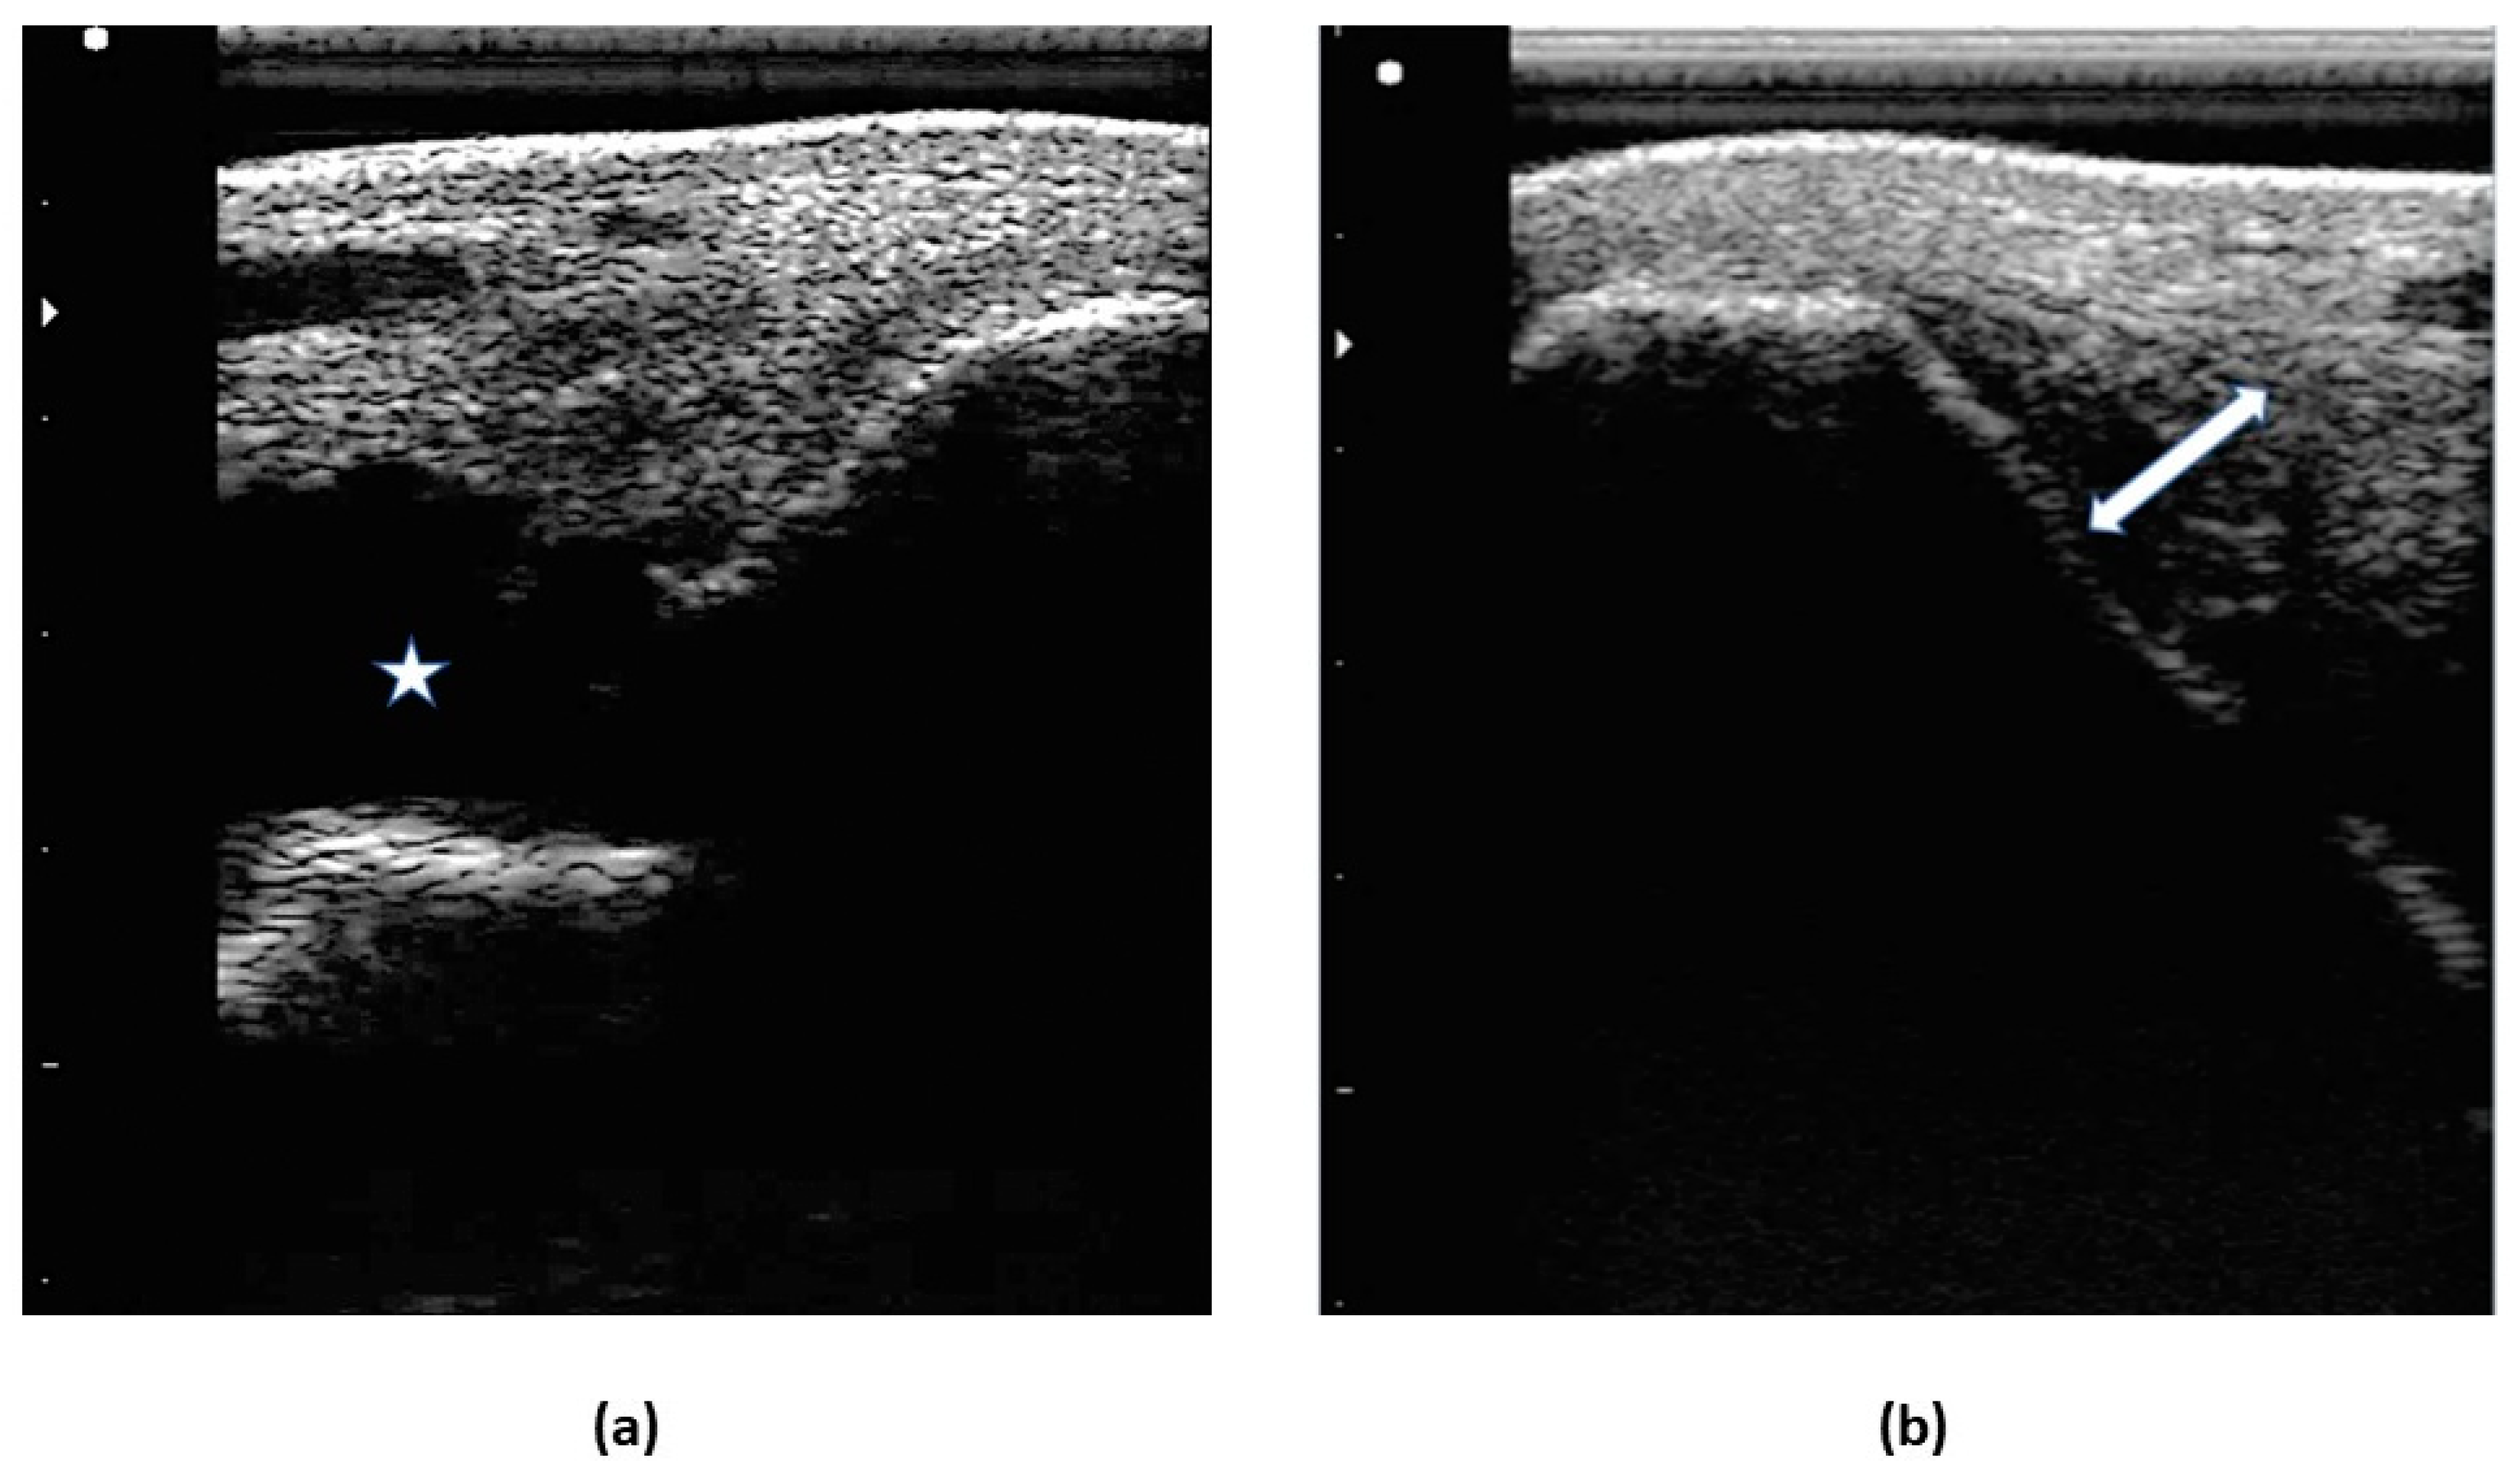

2.4.2. Ultrasound examination

3.1.2. Ultrasound examination